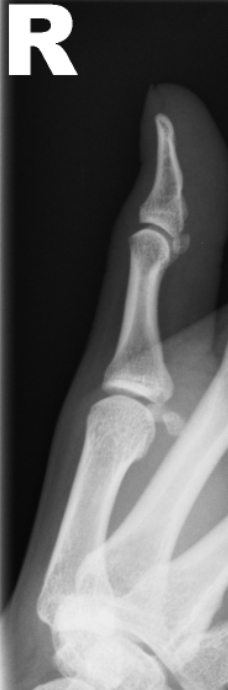

Female aged 28.

Fell on the outstetched hand. Considerable pain in and around the thumb metacarpal (MC)..

No localised wrist, nor snuff box, tenderness. A tender 1st MC with some swelling.

Is there a bone or joint abnormality present?